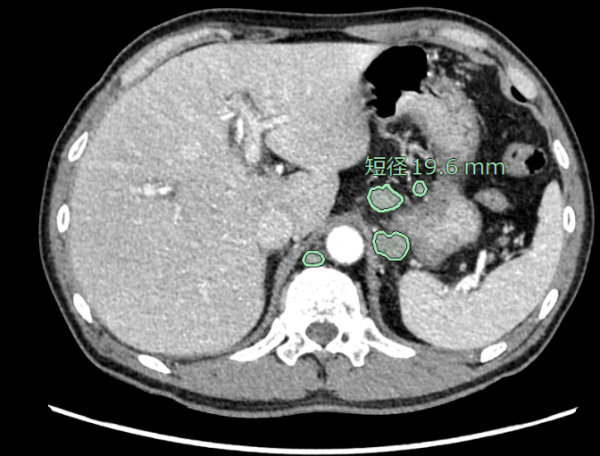

CT頸部・腹部リンパ節抽出

リンパ節は全身に存在しており、想定外の箇所が腫大することもあるため、読影に大きな負担がかかっている。従来、CT画像(造影・非造影)において、縦隔・腋窩リンパ節の抽出が可能だったが、今回、頸部・腹部(大動脈周囲、骨盤部)でもリンパ節の抽出ができるように対象範囲を拡充した。縦隔・腋窩だけではなく、頸部・腹部も含めた箇所における腫大傾向のリンパ節を拾い上げ、自動で短径計測を行う。癌の転移検索の支援に繋がることが期待される。